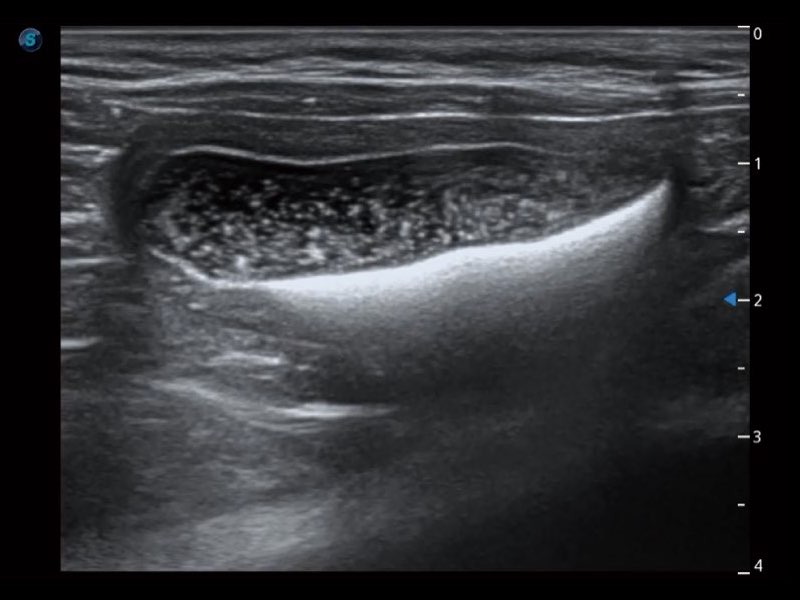

Przy pracach nad aparatem ProPet 60 uwzględniono najważniejsze preferencje i potrzeby weterynarzy, oferując finalnie przystępne cenowo i odpowiednio wyważone połączenie znakomitej precyzji klinicznej, zwiększonej wydajności i przemyślanego przebiegu pracy, niezastąpione w codziennej praktyce weterynaryjnej. Dzięki dostępowi do pełnej gamy głowic HD rozwiązanie to spełnia wszystkie potrzeby w zakresie obrazowania, umożliwiając wykonywanie badań jamy brzusznej, małych narządów, ortopedycznych, badań podczas rozrodu, a nawet badań serca i klatki piersiowej, a to wszystko przy doskonałym stosunku jakości do ceny.